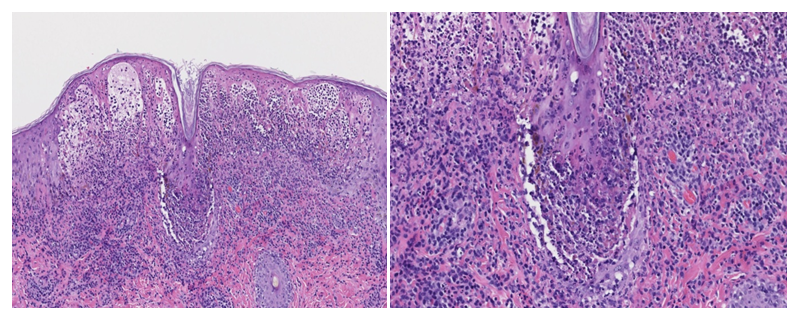

Skin examination revealed diffuse hemorrhagic vesiculopustules in different stages of healing involving the trunk, extremities, and face (Figure 1A)(Figure 1B). A skin punch biopsy from the right leg showed features of PLEVA with a lymphocytic infiltrate along the dermoepidermal junction, RBC extravasation, and epidermal necrotic keratinocytes. There was marked subepidermal edema with inflammatory cells and interface dermatitis, which extended down the hair follicle with intraepithelial apoptotic cells, but distinct herpetic viral cytopathy was not appreciated (Figure 2)(Figure 3). However, varicella-zoster virus (VZV) was detected by PCR from this skin site. The patient had elevated IgM titer to varicella, but no detected IgG antibodies to VZV. The patient was then diagnosed with primary varicella (chicken pox) and discharged on Valacyclovir 1gm TID for 7 days. At follow-up visit one-week later lesions were resolving.

Figure 2 C&D Higher power (10x & 20x) H&E section showing marked subepidermal edema with inflammatory cells extending down the hair follicle with interface dermatitis and apoptotic cells.